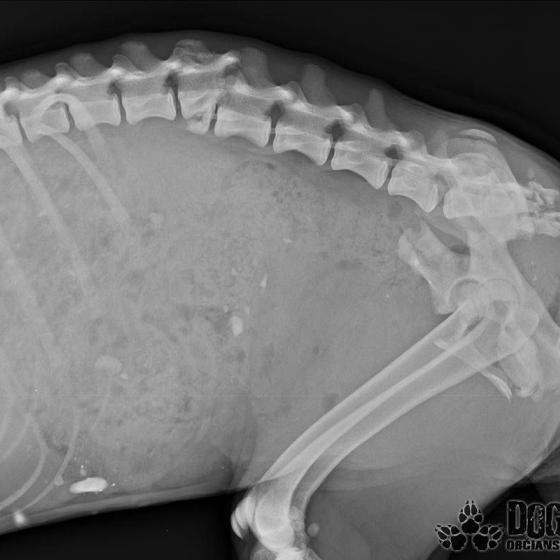

Mira, tak sme ju pomenovali.. Bola jednoducho úžasná.. Stalo sa však jedného dňa, že ju opustili.. Opustili a nechali napospas krutému osudu.. Nechápala a vybrala sa teda hľadať svojho človeka tam, kde ich bolo najviac.. Na vlakovú stanicu.. Vtedy ešte nepoznala ľudskú ľahostajnosť, iba lásku išla rozdávať.. Dni ubiehali jeden za druhým a nikto si po ňu neprišiel, nikto jej nepomohol.. Nenašiel sa ani jeden človek, ktorý by ju vzal do bezpečia pred rýchlym vakom.. V nepozornosti vybehla na koľajnice práve vtedy, keď vlak prichádzal.. Nie, ani po zrážke s vlakom jej nikto nepodal pomocnú ruku.. Musel ubehnúť týždeň, kým sa našla jediná dobrá duša, ktorá privolala pomoc.. Toto mladé a úchvatné dievčatko prežilo jeden celý týždeň s rozmliaždenou panvou, zlomenou chrbticou a poranenou miechou.. Neprestalo však čakať na svojho človeka, neprestávala dúfať, chcela žiť! Ľudia ju však iba obchádzali a odháňali..

Pomoc pre Miru žiaľ prišla neskoro.. Dnes poobede vraj ešte ako tak stála na nohách, ale večer okolo 22:00 keď sme dorazili, sa už postaviť nevedela. Našli sme ju zalezenú a premrznutú v plechovej búde.. Nedokázala si udržať stolicu, nedokázala sa samostatne vymočiť.. Miecha sa jej roztrhla.. Okamžite sme s ňou utekali do Bratislavy na kliniku, ale bolo neskoro.. Miruška musela mať neznesiteľné bolesti, ale tíško čakala a verila, lebo konečne bol pri nej človek, ktorého tak zúfalo hľadala..